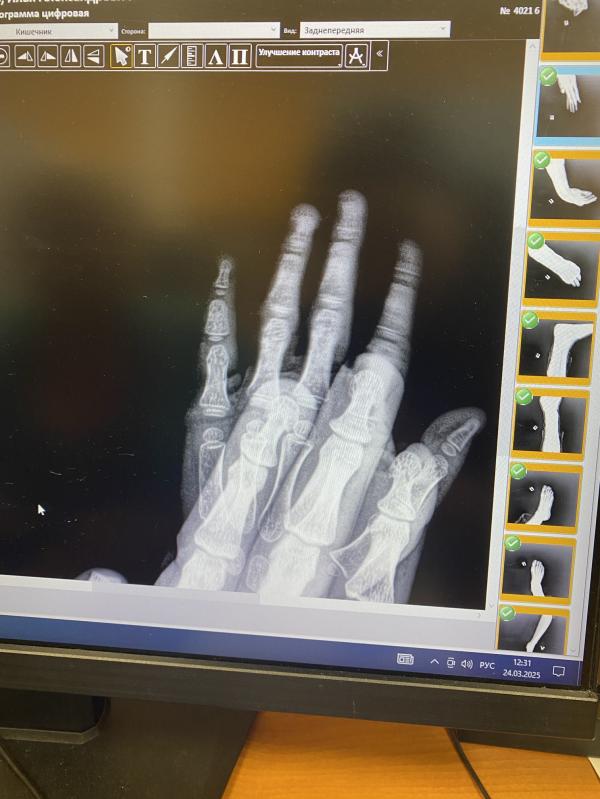

Трещина в мизинце у ребёнка: что делать маме?

Сын защемил палец в двери, сказали трещина

Защемил мизинец